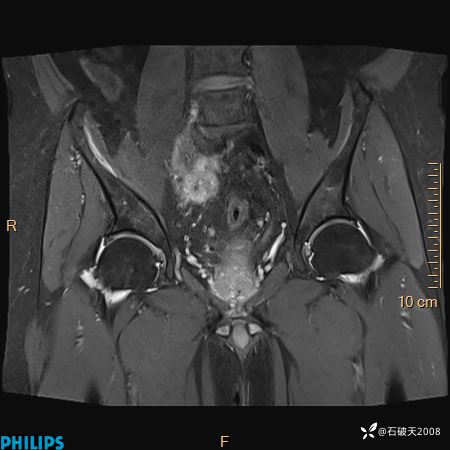

2023年3月份MRI影像

T2压脂冠状位